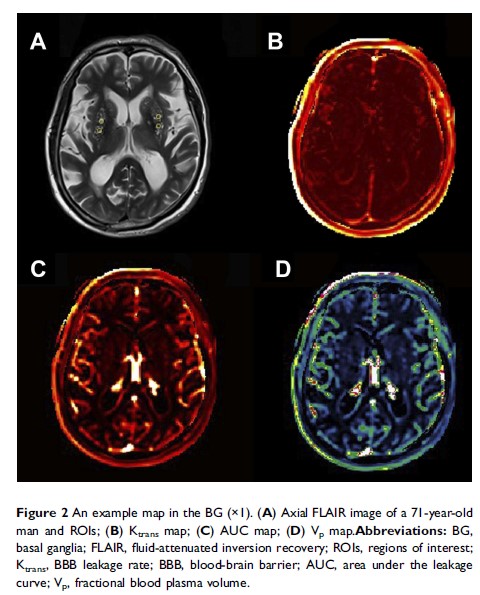

Original Research

- 作者:Yue Li, Man Li, Lei Yang, Wei Qin, Shuna Yang, Junliang Yuan, Tao Jiang, Wenli Hu

- 期刊:Clinical Interventions in Aging